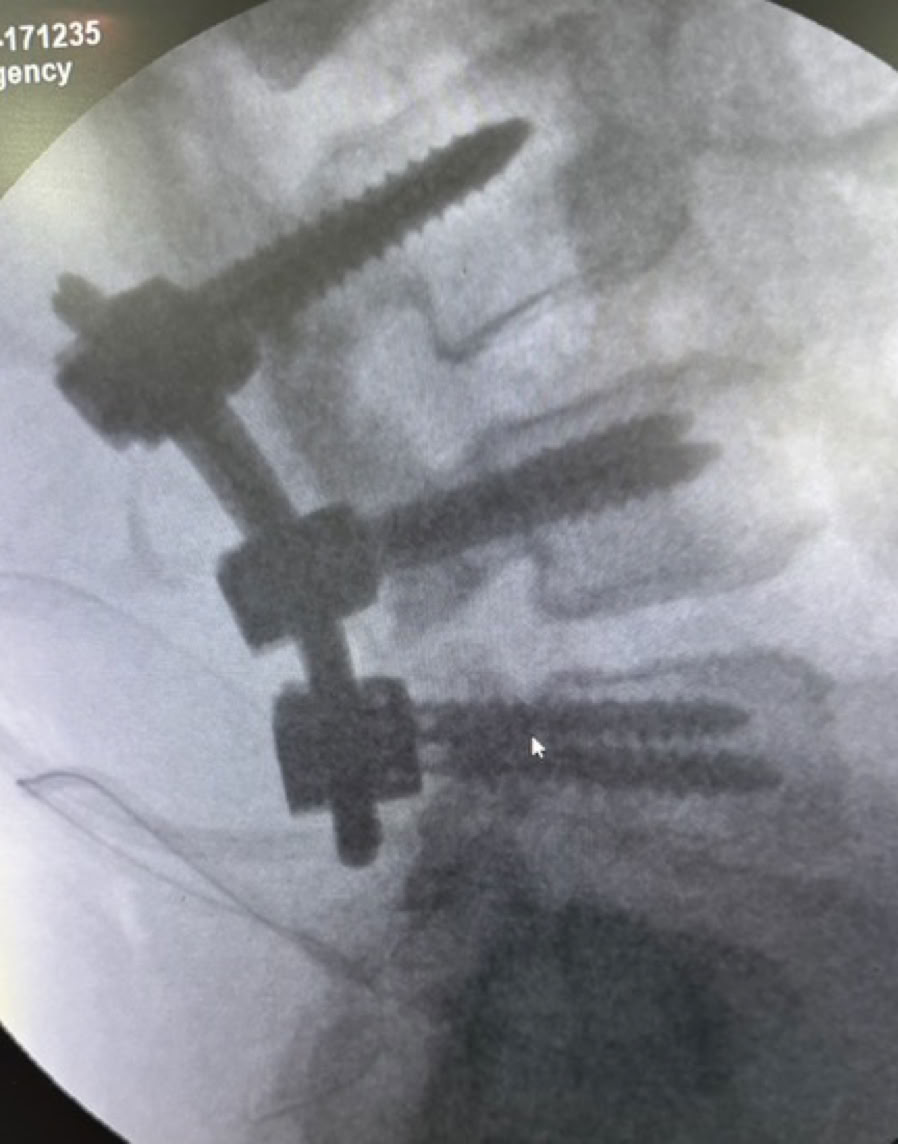

La ronda se vio interrumpida por la llegada de un politraumatizado por un tráfico, con las consiguientes fracturas abiertas múltiples de miembros inferiores, lo que nos permitió entrar en faena esa misma tarde para su estabilización e ingreso.

Con el volumen de trabajo pendiente decidimos empezar a operar el domingo 13 y el lunes 14 de julio con un quirófano mañana y tarde para poder atender también a la consulta y a partir del martes 15 hasta el viernes 19 funcionando con 2 quirófanos mañana y tarde para completar un total de 32 cirugías en 29 pacientes. Las reuniones de última hora de cada día para decidir el parte del día siguiente siempre han sido un agradable y fascinante ejercicio de prioridades, ciencia y posibilidades logísticas con aportación e implicación de todos

La impresión personal del que escribe estas líneas cuya ultima experiencia fue la expedición 49 en septiembre de 2019 es que el cambio a mejor ha sido radical . Las nuevas instalaciones quirúrgicas , el material para operar , los arcos de rayos, los procedimientos  y sobre todo la profesionalidad y el grado de autonomía del personal local demuestran que estas 102 expediciones, la labor de COEM y de todos sus voluntarios, junto con el trabajo constante de las Siervas de María lideradas por Sor Pilar y Sor Teodora han conseguido el admirable objetivo de montar un Servicio de Traumatología eficaz en el Hospital Notre Dame de la Santé en Dschang.